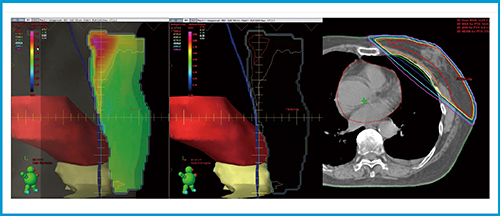

(3) 計算されたフルエンスマップを元のstructure setに戻し線量計算(dose calculation)を行う。線量計算用structure setに戻した時のフルエンスマップ,および線量分布を図4に示す。当院では105%線量(50Gy処方の場合52.5Gy)以上の領域をなくす努力をしている。図4の中央に示した茶色の領域が,105%以上の領域となる。

(4)〜(6)の手順を行った最終的なフルエンスマップと線量分布を図5に示した。

図4 最適化計算用structure setを線量計算用structure setに変更し線量計算した結果

左と中はフルエンスマップ,右は線量分布である。

図5 フルエンスマップを修正後の線量分布

心臓,消化管,対側のフルエンスを削除し,105%線量以上のフルエンスを減少させた。